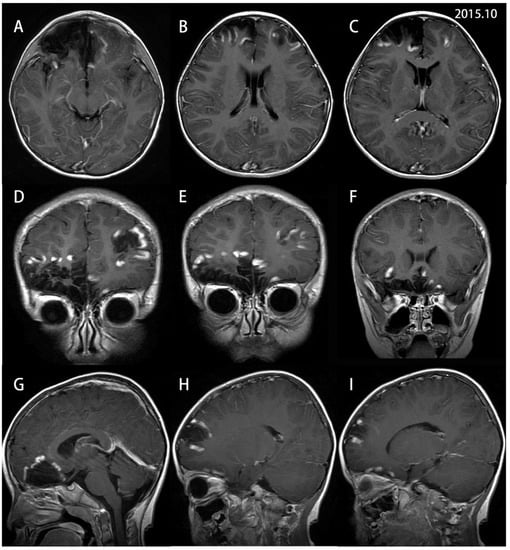

2. Case Report